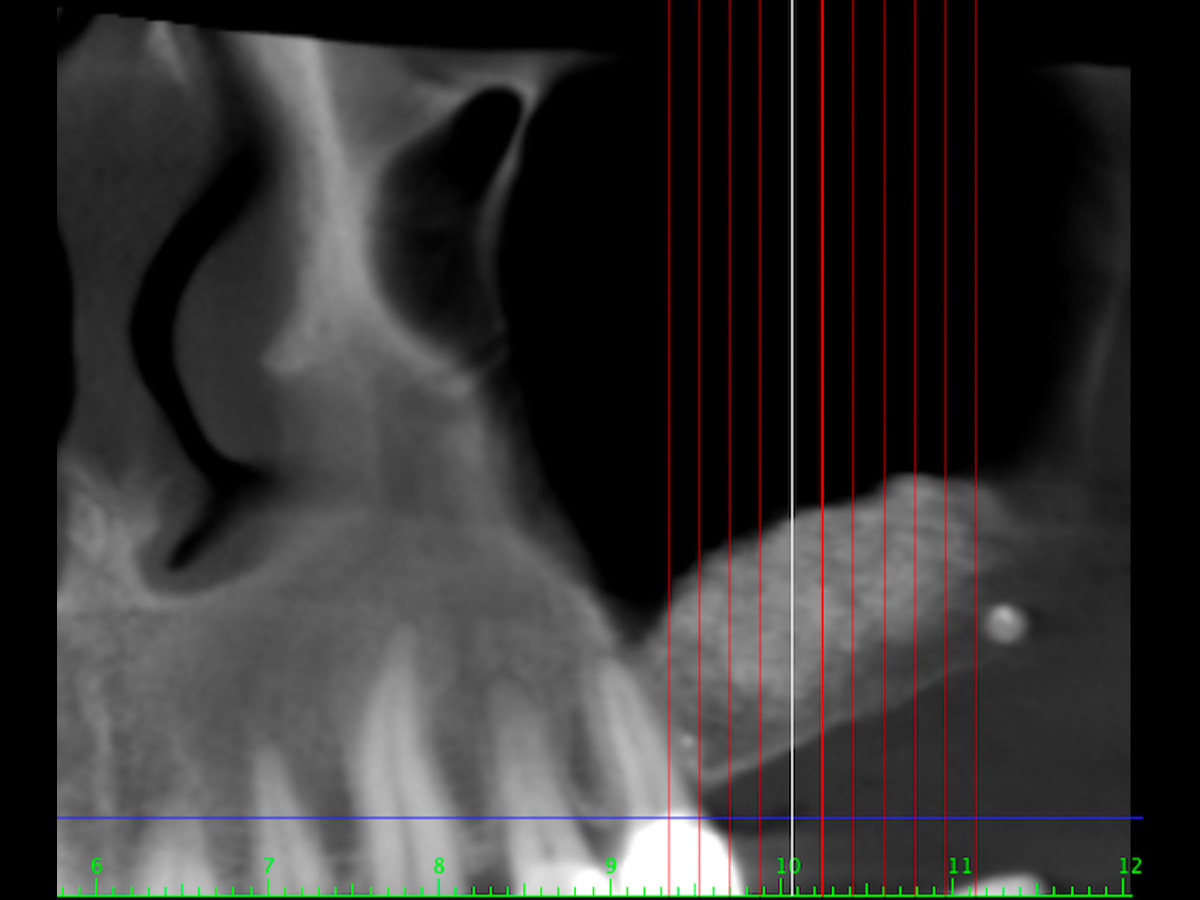

Abbildung 4

DVT vor Implantation (Ausschitt).